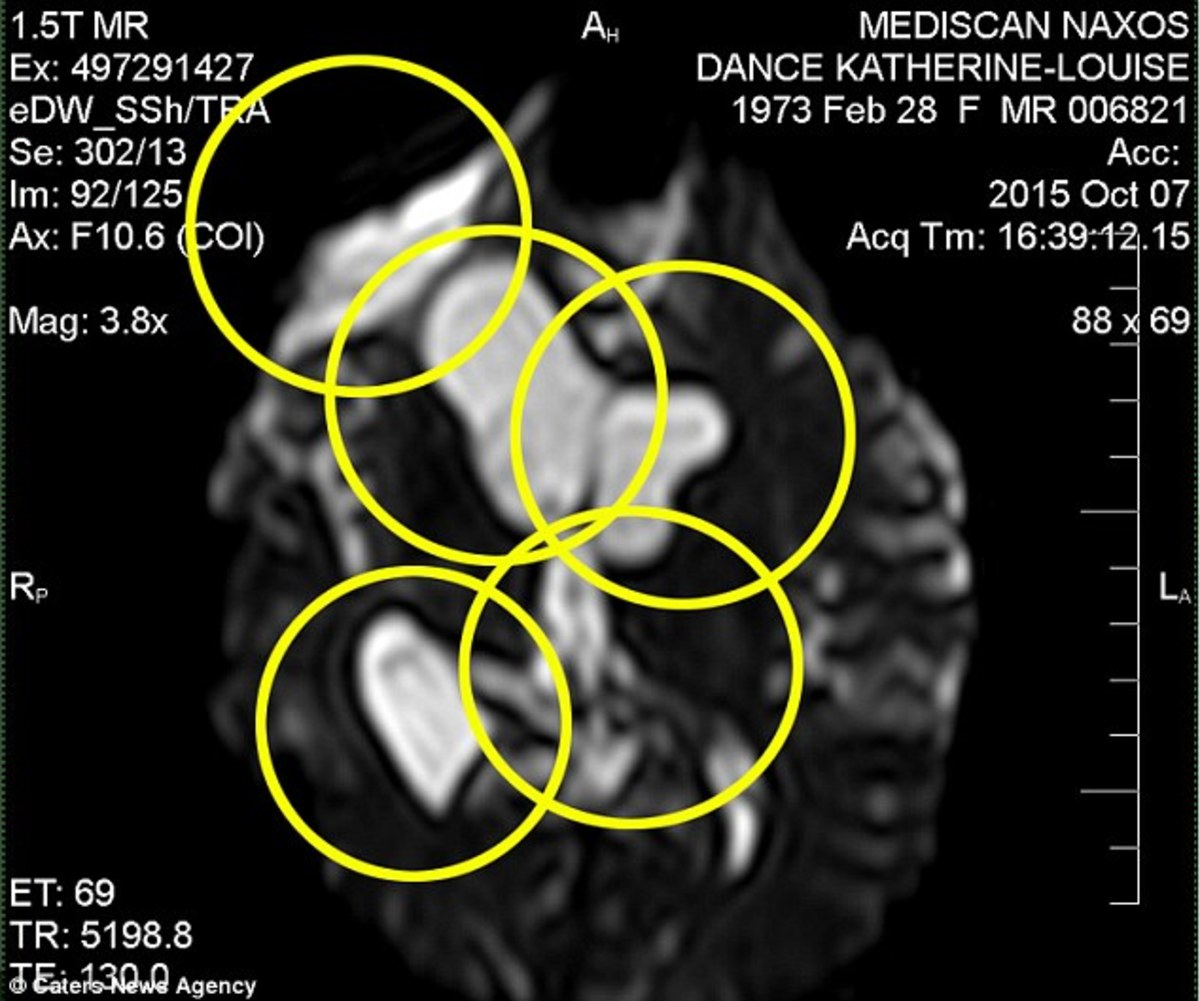

20+ Brain Tumor Eye Test US. Following are some general signs and symptoms. A regular, routine eye test can sometimes detect eye problems that indicate the presence of a brain tumour before any symptoms become obvious.

The eye test initially detected just one tumour, but while under examination at the princess alexandra eye pavillion, a second brain tumour was detected. Noncancerous brain tumors don't spread, but they can grow and cause symptoms. They can't spread to other parts of your.